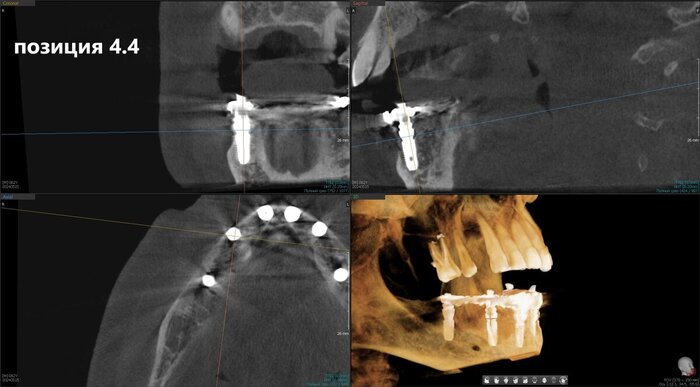

Имплантаты установлены и пациент отправляется на КЛКТ. Каждый раз очень радуется имплантолог, что аппарат находится в клинике. Я тоже рада)

Позиция 4.6

Имплантолог видит, сколько мм можно докрутить безопасно для структур челюсти (нервов, сосудов). Делает дело.